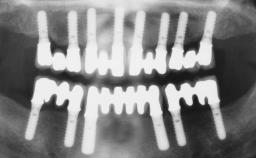

Immediate Loading of Six Implants in the Mandible and Six Implants in the Maxilla and Final Restoration with Full-Arch CAD/CAM Metal Framework FDPs Involving Digital Planning and Guided Surgery

Ali Tahmaseb, Renaat De Clerck, Daniel Wismeijer

# of Implants 12

Type of Implants One-Piece